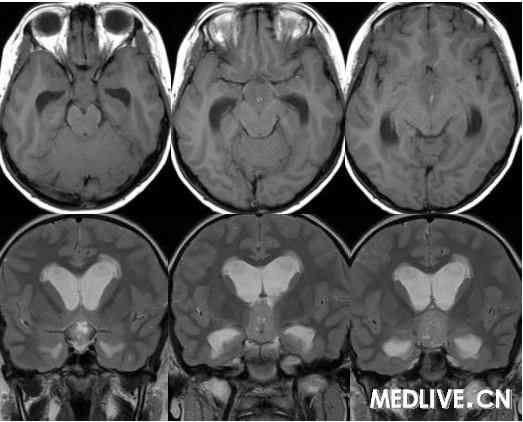

解答详情: 生殖细胞瘤由原始的生殖细胞衍生而来,好发于松果体区,其次为鞍上池。肿瘤多发生于男性青少年,位于鞍上生殖细胞瘤则以女性多见。生殖细胞瘤对放射线非常敏感。该瘤通常无包膜、无钙化、出血、坏死或囊性变,属低度恶性肿瘤,多呈浸润性生长,常有不同程度和形式的转移,易向蛛网膜下腔及脑室系统种植、播散。组织学上,肿瘤主要含有两种细胞成分:上皮样细胞和淋巴样细胞。 1、CT表现:  ①肿瘤最常见于松果体区,位于鞍上区肿块常累及漏斗;  ②CT平扫多呈等密度或稍高密度肿块,无出血、坏死及囊性变,可分叶,但境界清楚;瘤体本身钙化少见,典型松果体区生殖细胞瘤常见肿瘤包埋松果体钙化灶。  ③增强扫描呈中等至明显的均匀强化。  ④室管膜下转移可表现为沿脑室壁线状或条片状强化,沿脑脊液向蛛网膜下腔播散表现为脑表面、脑池的线状或结节状强化。   2、MR表现:  ①最常见于松果体区,也常见于鞍上,可同时或单独存在。②T1加权为略低信号或等信号,T2加权常呈等信号或高信号。③增强后;呈明显均匀一致强化,并能发现沿脑脊液或室管膜转移的病灶。鉴别诊断  1、颅咽管瘤:多为囊性或囊实性肿块,钙化多见。纯实性者可呈稍高密度,并可强化,与生殖细胞瘤不易鉴别、  2、星形细胞瘤:一般肿瘤较大,密度偏低,后期可出血,肿瘤通常位于下丘脑,并沿视交叉或视束延伸,可在眼眶内形成肿块。  3、垂体瘤:发生于鞍内,但可向鞍上生长,小儿罕见,肿瘤易出血、坏死,鞍底骨质变薄、下陷,海绵窦常受累。 生殖细胞瘤。4、脑膜瘤:好发于成人,儿童罕见,肿瘤部位偏前,伴骨质增生、硬化及蝶窦过度气化。